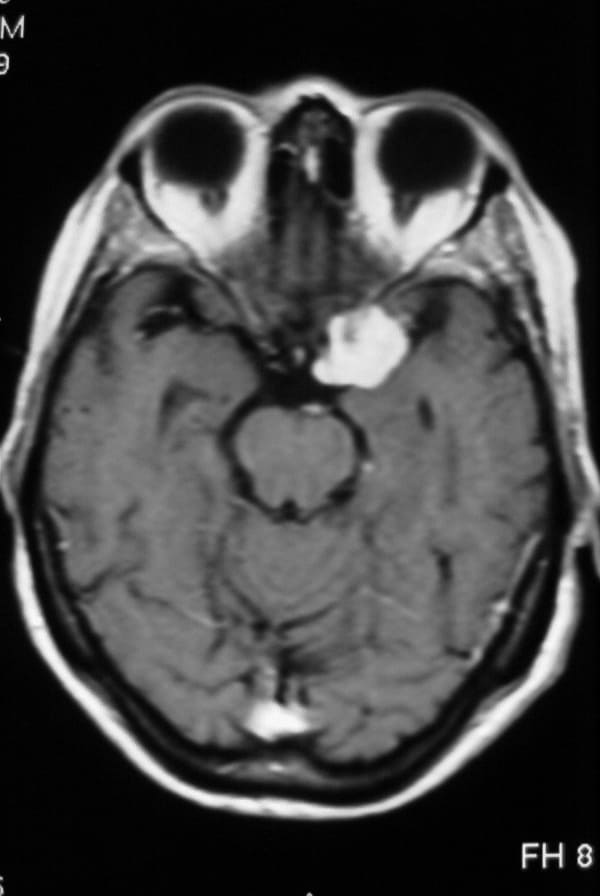

• RM cerebral